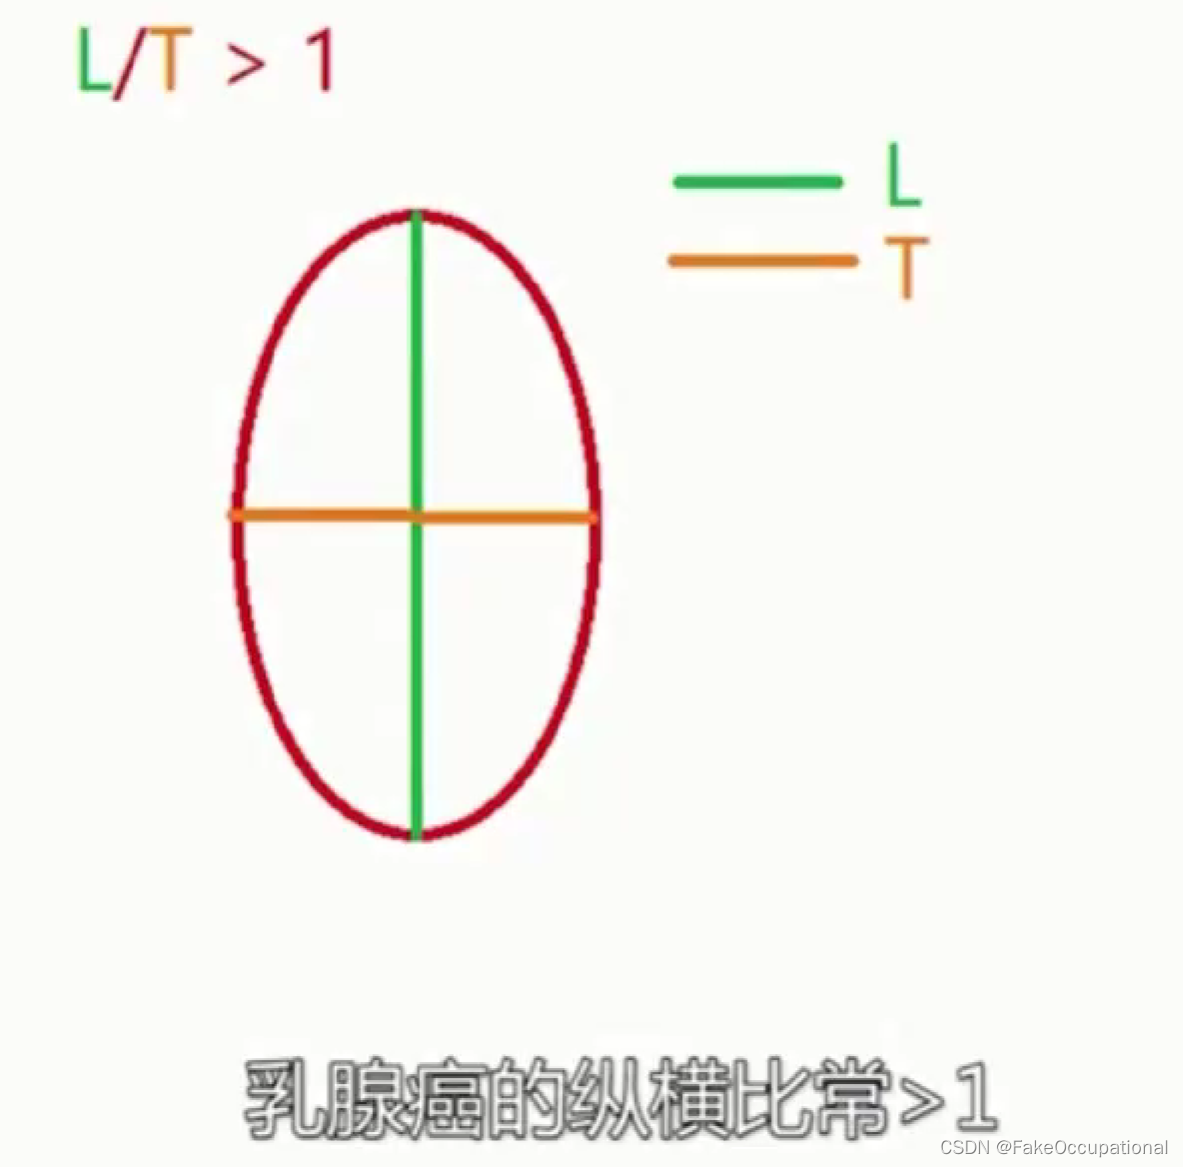

乳腺癌

- 其理论依据是恶性肿瘤常星离心性生长